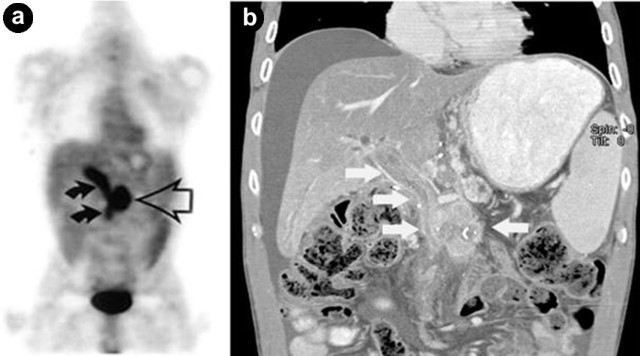

a) Pancreatic Metastasis from Head and Neck Cancer

Head and neck cancer is the sixth most common carcinoma in the world. Patients with head and neck cancer are well-known to have synchronous/ metachronous second primary malignancies. Despite improved local control of head and neck cancer recently, there is no increase in survival rate because of the high mortality rate from distance metastases and second primary malignancies. The incidences of distance metastases and second primary malignancies are ranging from 4% to 25% [7]. The common sites for metastases are lungs, bones, and liver; pancreatic metastasis is rare. For staging, when compared to the limited field of view of CT and MRI, PET/CT is the best imaging modality because of its ability to evaluate the whole body (Figure 9) [7]. The sensitivity, specificity, and negative predictive value for detecting distance metastases and second primary malignancies were 98%, 93%, 100%, respectively; however, the positive predictive value was only 63% [8]. As a result, additional test (i.e. biopsy) is needed to rule out false-positive result.

|

Figure 9. a. Coronal PET maximum intensity projection image shows a large, advanced head and neck squamous cell cancer with metastasis to the thoracic spine, liver, and head of the pancreas (arrows). b. Fused axial PET/CT image identifies the corresponding hypermetabolic pancreatic lesion (crosshair). |